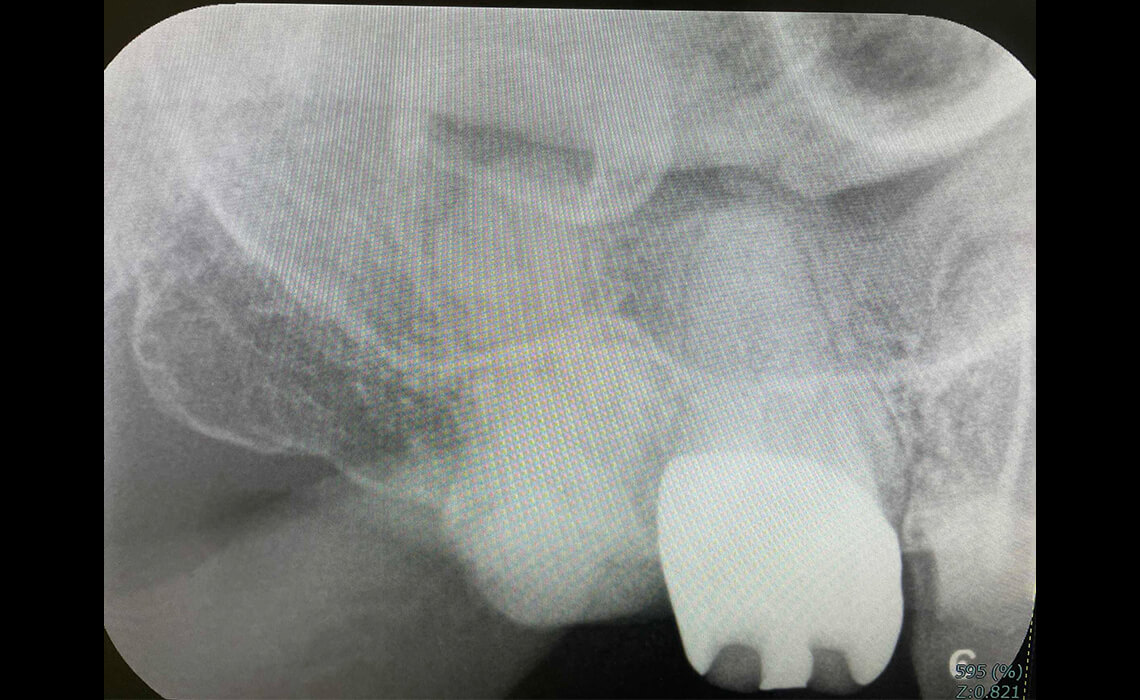

根管治療の最後の仕上げとして「根管充填」というものがあり、これは、歯の神経を取ったことにより空洞になった根管内を、緊密に塞ぐことを指します。

この隙間を塞ぐことができなければ、これが原因となり数年が経過した時に再び感染してしまうことがあります。一般的には「ガッタパーチャ」と呼ばれる、ゴムのようなもので隙間を塞ぐのですが、根管内は複雑な構造になっていますので、隙間を残してしまうことがあるため、再治療を行うケースが多いのです。

それに対して、「MTAセメント」と呼ばれるものは隙間を塞ぐことができ、かつ、殺菌作用及び強い接着性、歯の組織を再生させる効果があるため、治療後の経過が非常に良好になります。当院では、根管の高い封鎖性、適合性、歯と一体になる再石灰化性を持つMTA系セメントを使用しています。

CASE